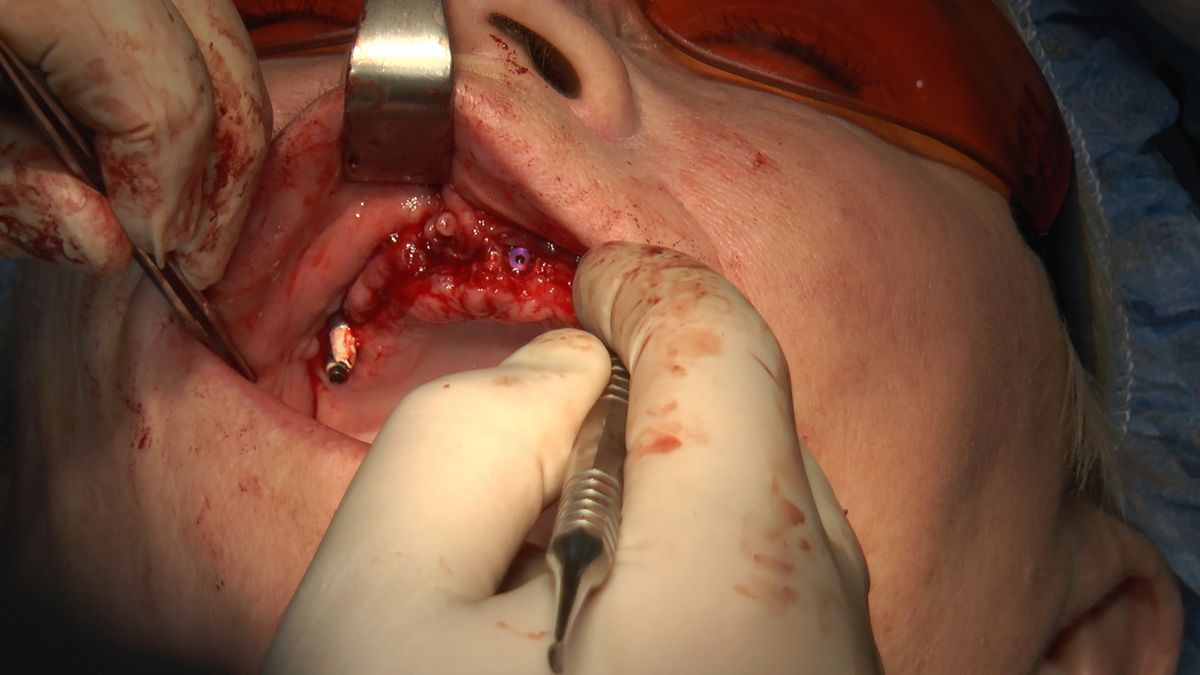

W ostatni weekend czerwca 2018 roku kursanci II Sezonu Preludium Implantologii odbyli piątą, finałową sesję, która w całości podporządkowana była praktyce. W ciągu dwóch dni zabiegowych Lekarze uczestniczący w szkoleniu przeprowadzili szereg zabiegów pod kierunkiem dr n.med. Violetty Szycik. Wszczepili 17 implantów oraz przeprowadzili ekstrakcje i zabiegi regeneracyjne kości. Zabiegi były wykonywane także w sedacji dożylnej z udziałem specjalisty anestezjologii i intensywnej terapii dr Jolanty Grzybowskiej. Preludium implantologii to nowy program edukacyjny dla adeptów implantologii stomatologicznej, którego celem jest wprowadzenie do implantologii poprzez pozyskanie wiedzy w szerokim zakresie i uwzględnieniem szczegółów mających decydujące znaczenie dla powodzenia leczenia implantologicznego. Ale tak jak wszystkie szkolenia w Instytucie Vivadental, w tym wiodące Practiculum Implantologii, zorientowane jest na praktyce i samodzielnym wykonywaniu zabiegów pod kierunkiem Mentora. To najlepsza edukacja w medycynie zabiegowej, a zarazem najlepszy start do implantologii.